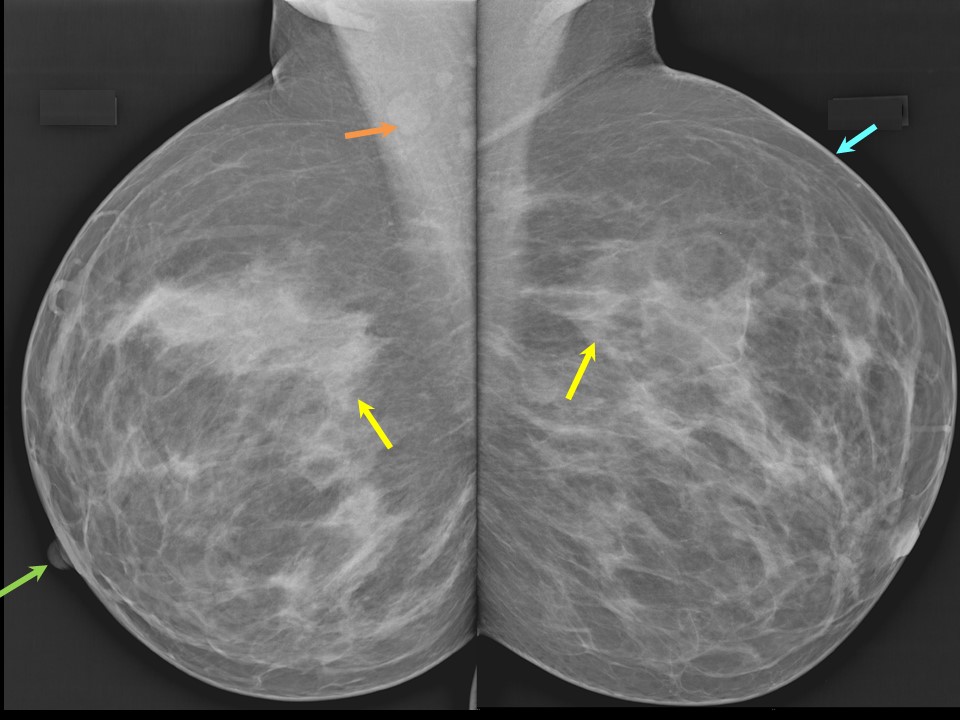

Феномен гипердиагностики в маммографии: примеры и иллюстрации

Раздел: Образы вокруг